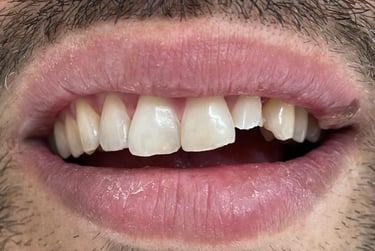

Aspecto Clínico Inicial - Fotografias originais — nenhuma contém retoques

Coroas em Dissilicato de Lítio

Todos os caso a seguir estão associadas a clareamento dentário

Antes